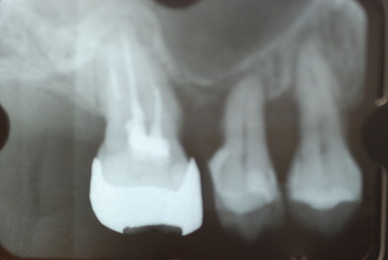

![0a9e48b6-s[1]](https://livedoor.blogimg.jp/netdental/imgs/4/0/40e1507e.jpg)